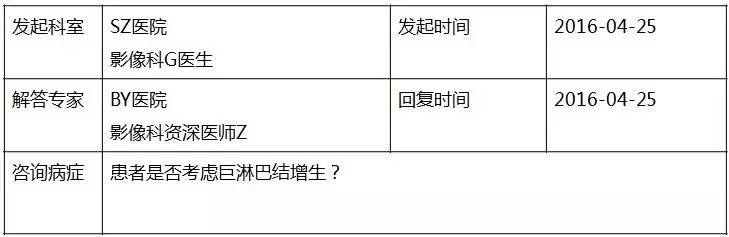

▼患者CT平扫(右)及增强CT(左)检查报告资料

Z主任 甲状腺肿大,内见弥漫多发结节,界限不清,甲状腺包膜毛糙。双侧颈部、锁骨上、纵隔多发肿大淋巴结,病变均强化明显,密度不均,边缘毛糙,考虑甲状腺恶性肿瘤伴多发淋巴结转移,或甲状腺内也是转移瘤。Castleman病多灶者少见,一般病变边缘光整,也不会累及甲状腺。建议穿刺活检。 C主任 双侧甲状腺肿大,密度不均,不均匀强化,甲状软骨未见明显骨质破坏气管右侧壁受压;双侧颈部多发肿大淋巴结,不均匀强化;考虑为甲状腺恶性占位性病变伴双侧颈部淋巴结转移,建议组织学进一步检查。 声明:以上资料均来自和缓名医平台的真实案例,为保护用户隐私,均用化名代替。资深医师Z咨询反馈